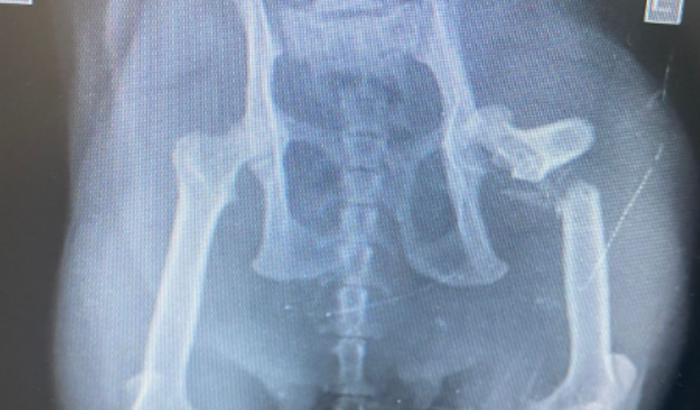

Venho por meio da vakinha.com,pedir ajuda por meu gato bigodinho que foi atropelado e quebrou a bacia e fêmur e precisa de uma prótese,Peço humildemente a ajuda de vocês muito obrigado.deus abençoe ver tudo

Venho por meio da vakinha.com,pedir ajuda por meu gato bigodinho que foi atropelado e quebrou a bacia e fêmur e precisa de uma prótese,Peço humildemente a ajuda de vocês muito obrigado.